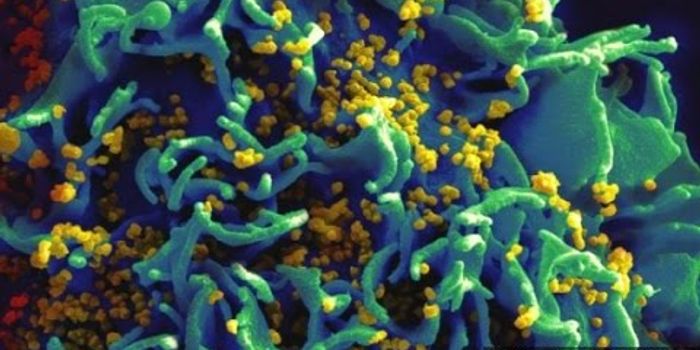

NOV 28, 2018Health & MedicineDecember 1 marks the 30th anniversary of World AIDS Day. Acquired immunodeficiency syndrome (AIDS) is a chronic, potenti ...